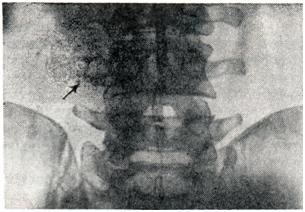

Рис. 4.

Актиномикоз забрюшинной клетчатки (фистулограмма).

Второе по частоте направление распространения актиномикоза из слепой кишки — в забрюшинную клетчатку (рис. 4) — ретроабдоминальный актиномикоз. Ретроабдоминальный актиномикоз характеризуется необычной для этой инфекции диффузной инфильтрацией клетчатки, отсутствием четких границ очага, значительным отеком окружающих тканей, гнойным расплавлением по типу флегмоны и часто осложняется амилоидозом внутренних органов. Один из наиболее постоянных клинических симптомов при ретроабдоминальном актиномикозе — псоит.